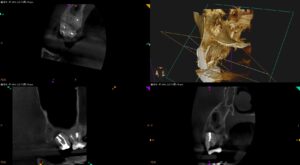

以前の治療の経過観察。 根管充填も、Intentional Replantationも、嵌めたい(充填したい)物を穴に嵌めようとすれば、はまる場所が嵌めたいものよりも大きくなければ、はまらない…〜#2 Intention … 続きを読む 根管充填も、Intentional Replantationも、嵌めたい(充填したい)物を穴に嵌めようとすれば、はまる場所が嵌めたいものよりも大きくなければ、はまらない…〜#2 Intentional Replantationとその2M recall